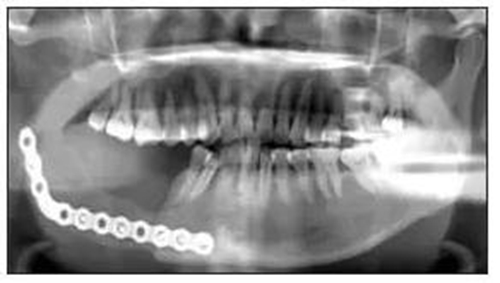

全景片、錐形束CT(cone beam computedtomography,CBCT)及螺旋CT結(jié)果提示:右側(cè)下頜骨體C6至下頜升支乙狀切跡區(qū)域可見(jiàn)一囊性病損,與正常骨邊界清楚,中心密度均勻,內(nèi)可見(jiàn)大小不等的分隔,邊緣呈切跡狀改變,病變累及乙狀切跡和喙突,向頰舌側(cè)膨隆明顯,舌側(cè)骨密質(zhì)不連續(xù),頰側(cè)骨密質(zhì)外可見(jiàn)骨膜反應(yīng),C78牙根有吸收。右下頜骨頰舌側(cè)不連續(xù)(圖1)。

圖1 患者術(shù)前檢查

A:全景片(箭頭所指為牙齒截根樣吸收);

B:螺旋CT平掃(箭頭所指為病變突破骨組織);

C:CBCT(箭頭所指為病變位置)。

免疫組織化學(xué)結(jié)果:S100彌漫陽(yáng)性、CD21陰性、CD57陰性、CR陽(yáng)性、結(jié)蛋白陰性、鈣調(diào)結(jié)蛋白陰性、ALK陰性、PCK陰性、Ki-67表達(dá)2%~5%陽(yáng)性(圖2)。1.5 隨訪患者術(shù)后切口愈合良好,牙無(wú)松動(dòng),咬合關(guān)系良好。術(shù)后復(fù)查顯示傷口愈合良好,骨斷端生長(zhǎng)良好(圖3)。

圖3 術(shù)后全景片